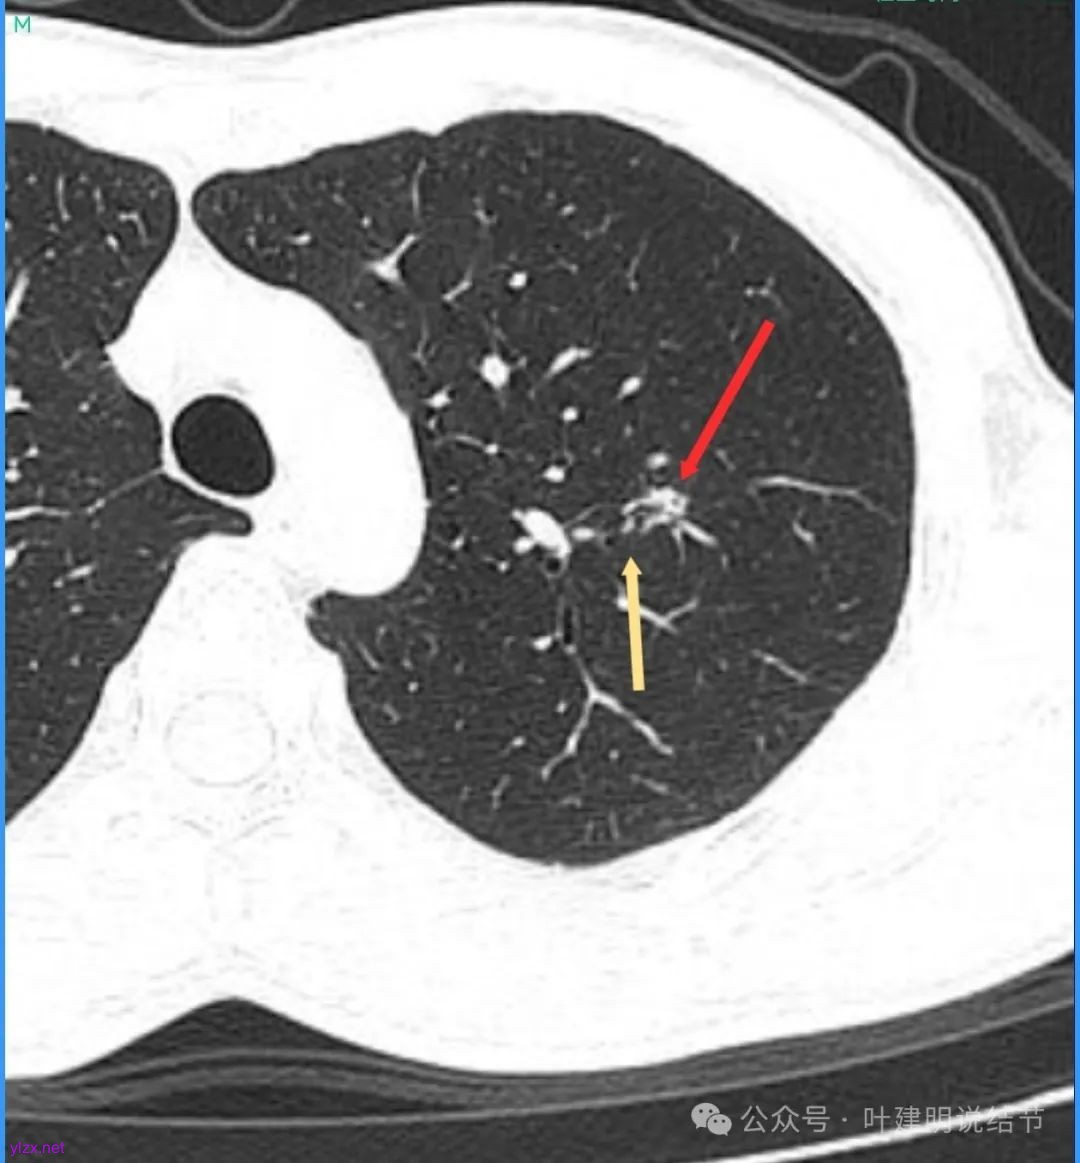

病灶密度不均,混合密度的样子,相应的细支气管有扭曲略显扩张。

边缘较为毛糙不平,灶内密度杂乱,细支气管穿行,整体轮廓较清。

邻近血管受结节影响,略向病灶侧弯,病灶处是扩张的细支气管还是灶内的空泡征?

有血管征,整体轮廓与边界较清,灶内有蜂窝状。

血管穿过病灶,灶内多个小空泡,整体轮廓较清。

蓝色部分似乎是血管,但似乎又是增厚的支气管壁,局部细支气管扩张。

特别上上图边缘些的层面,蓝色箭头所指的实性明显又像位于扩张细支气管内或与支气管壁一块的样子。